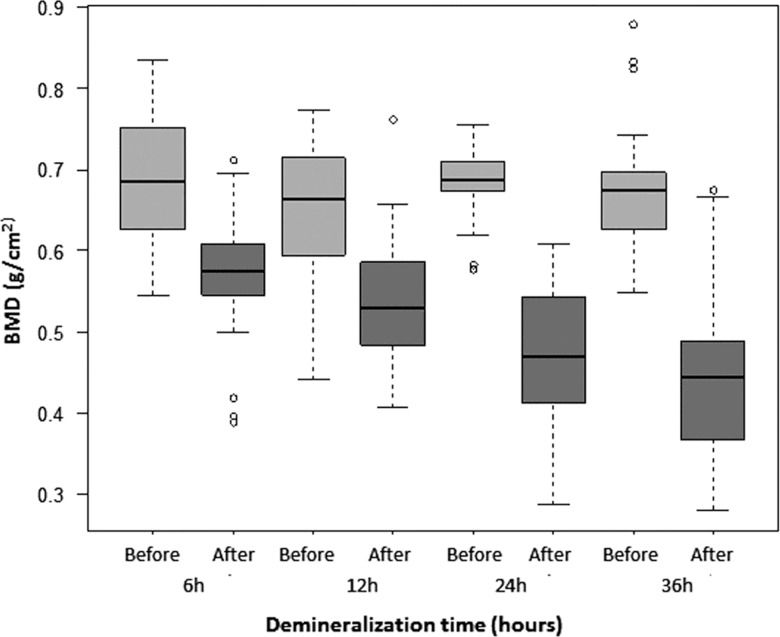

The mean pre-demineralization BMD ranged from 0.65 to 0.69 g/cm2 with no significant difference among groups. The post-demineralization BMD progressively decreased from 0.54 g/cm2 in G6 to 0.44 g/cm2 in G36, corresponding to 83.32%, 82.96%, 67.37% and 65.37% of the intra-group pre-demineralization values for G6, G12, G24 and G36, respectively, with significant differences (p<0.0001) between the pre- and post-demineralization values in all groups (Table 2, Figure 6). A significant difference was also observed for most comparisons of the post-demineralization values between groups (G6xG12: p=0.0245; G6xG24: p<0.0001; G6xG36: p<0.0001; G12xG24: p<0.0001; G12xG36: p<0.0001), but not for and G24xG36 (p=0.1381).

BMD (g/cm2) data (mean±SD, range, median) before and after demineralization according to demineralization time (hours).

| BMD | 6 h | 12 h | 24 h | 36 h |

|---|---|---|---|---|

| Pre- | 0.69±0.08 | 0.65±0.08 | 0.69±0.04 | 0.67±0.07 |

| (0.55 - 0.83) | (0.44 - 0.77) | (0.58 - 0.76) | (0.55 - 0.88) | |

| 0.69 | 0.66 | 0.69 | 0.68 | |

| Post- | 0.54±0.08 | 0.46±0.08 | 0.46±0.08 | 0.44±0.10 |

| (0.41 - 0.76) | (0.29 - 0.61) | (0.29 - 0.61) | (0.28 - 0.68) | |

| 0.53 | 0.47 | 0.47 | 0.45 |